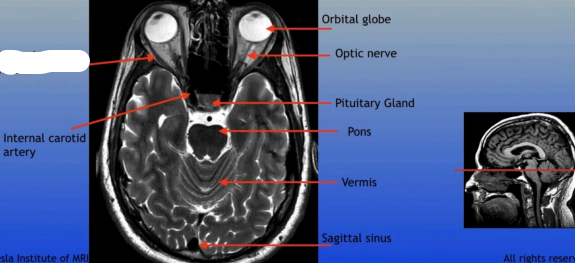

Internal Carotid Artery

Orbital Globe

Optic Nerve

Pituitary Gland

Pons

Vermis

Sagittal Sinus